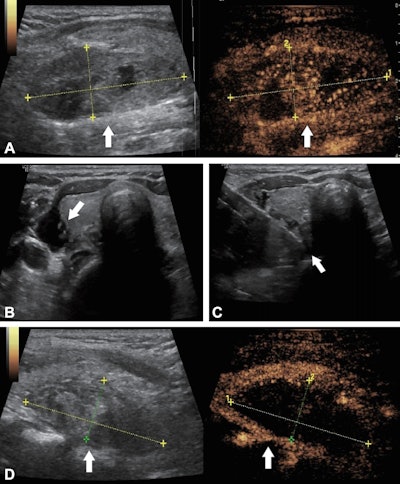

Ultrasound images in a 56-year-old woman with primary hyperparathyroidism treated using ultrasound-guided microwave ablation. (A) Preablation longitudinal images reveal a hypoechoic parathyroid nodule (arrow) measuring 4.84 × 1.86 × 2.53 cm. The B-mode image (left) shows the nodule, while the contrast-enhanced image (right) demonstrates hyperenhancement of the solid component of the parathyroid lesion. The coordinate axes indicate the measured maximum diameters of the nodule. (B) Transverse image shows percutaneous injection of saline solution (arrow) with ultrasound guidance, to create an isolation zone to protect surrounding tissues. (C) Transverse image shows the ablation needle (arrow) positioned within the nodule for microwave ablation. (D) Postablation longitudinal images of the lesion area (arrow). The B-mode image (left) shows the hyperechoic lesion area, while the contrast-enhanced image (right) shows no contrast enhancement, indicating complete ablation. The coordinate axes indicate the maximum diameters of the ablation zone (4.51 × 1.85 × 2.04 cm).RSNA